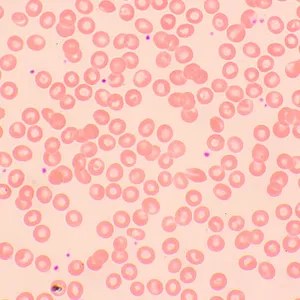

Микроскоп MAGUS Bio 250BL может использоваться и для рутинной работы в лаборатории, и для научных исследований, и для обучения студентов. Он предназначен для работы с тонкими срезами и мазками биологических образцов в проходящем свете. Основной метод наблюдений – светлое поле, но возможно и использование темного поля, поляризованного света и фазового контраста (при установке дополнительных компонентов).